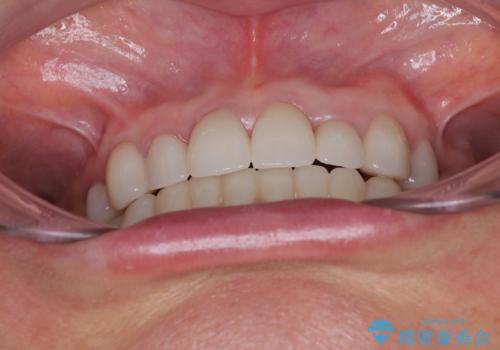

前歯のデコボコおよび奥歯の咬み合わせを改善するために、上顎左右の小臼歯を欠損スペースを利用して歯列を整え、矯正治療後に気になる上下前歯などをオールセラミッククラウンで美しく仕上げていくこととしました。

色や歯列が整ったことはもちろん満足いただけましたが、上顎の舌側転位していた前歯が綺麗に整ったことで違和感が減ったことを非常に喜んでいらっしゃいました。